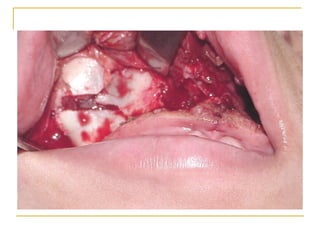

Infiltración supraperióstica Esta indicada cuando los procedimientos dentales están confinados a áreas circunscritas Se deposita la solución anestésica en el área en que se desea intervenir. Para piezas dentarias se inyecta en el fondo del vestíbulo, frente al ápice, con el bisel de la aguja hacia el hueso y en forma supraperóstica (el periostio dañado provoca mucho dolor).

Infiltración supraperióstica Nervio anestesiado :  ramos terminales plexo dental Área anestesiada :  Pulpa, raíz, periostio, tejido conectivo, membrana mucosa Indicaciones:   Anestesia pulpar de dientes maxilares (TX 1 – 2 dientes) Anestesia tejidos blandos (Qx área circunscrita)

Infiltración supraperióstica Contraindicación: Infección o inflamación aguda local Ventajas: Alto índice éxito (95%) Técnica fácil de administrar Usualmente atraumática Desventajas :  No para áreas largas